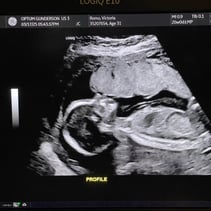

Greetings! I’ve been away from my updates for a couple of weeks, so lets get you caught up on all the things! First off, we had our Anatomy Scan today and hit the half way mark of the pregnancy. WOW. Our baby girl is doing so so well. From head to toe, she’s about 9-10inches and weighs 12oz. A week or two ago I stopped having all pregnancy symptoms besides the obvious physical changes. This was awesome but also made me a little uneasy. I also have not felt much movement and waiting 4 weeks for my 20 week appointment was starting to make me very antsy in a horribly, anxious way. Having a miscarriage the first time around has really made it difficult to relax and feel confident that everything is going well. Last week Steven went ahead and bought me a Doppler to listen to our baby’s heart beat at home while we waited for our next appointment. Once it came in and I found that wonderful sound of her heart, whew! Instant relief. Today was even better! Not only is SHE healthy, but so am I! I started going to the gym a few days out of the week and signed myself up for a 4 week Prenatal Yoga class that takes place every Saturday. My blood pressure today was 118/72 and weighing 129 which is 4 pounds more than my last appointment. I feel wonderful and even more excited than I was before to meet our girl! We’ve started clearing out the room that will be her nursery and are so grateful to the friends and family that have already started pouring their love into us and our baby with the registry gifts! Steven also surprised me with setting me up to visit family in Texas next month during my Spring Break from work. What a guy. 💕 I hope you all enjoy these photos! You‘ll see her profile with her cute little nose! There’s one of her foot, one of her crunched up with her legs bent, a crazy one of her that looks like a Halloween photo, and it’s hard to tell but one of her lips and nose. She was spinning and drinking and kissing us while she was having her first photoshoot. I will start feeling her more in the next couple of months. I have an anterior placenta so it makes things a little harder to feel since its placed in the front of my uterus. She is having fun, nonetheless. That’s all for now! We love you aaalllllll. A note from Steven: we could clearly tell during the sonogram that she gets her dance moves from her daddy.